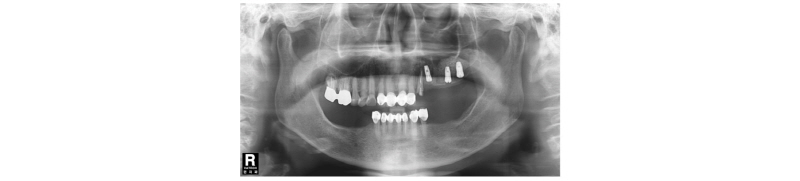

Fig. 1. First visit. Panoramic x-ray view. |

Fig. 2. Pre-Op. Panoramic x-ray view. |